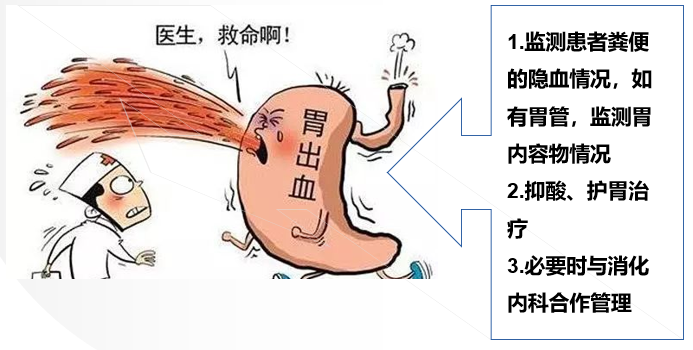

④消化道出血